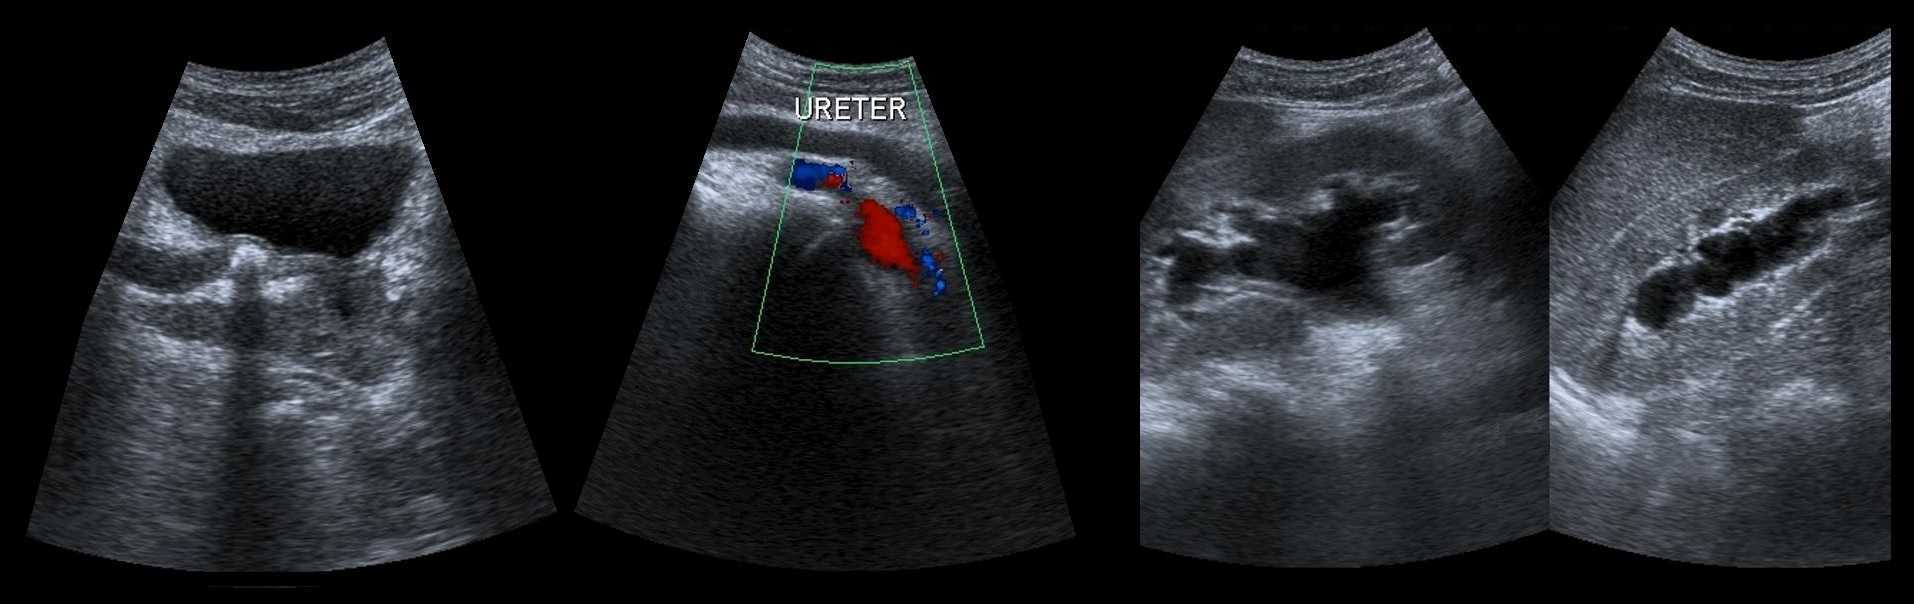

Мочевой пузырь и дистальный отдел мочеточника на УЗИ

В положении пациента лежа на спине в надлобковой области выводим мочевой пузырь. Оцените наполнение мочевого пузыря и дистальный отдел мочеточников. В норме дистальный отдел мочеточника не видно. Мочеточник более 7 мм в диаметре — мегауретер.

Рисунок. На УЗИ расширенный дистальный отдел мочеточника (1, 2, 3). Про уретероцеле (3) подробнее смотри здесь.

Рисунок. Пациент с острой почечной коликой. На УЗИ слева в дистальном отделе мочеточника гиперэхогенное округлое образование с акустической тенью (1), мочеточник расширен на всем протяжении (2), лоханка и большие чашечки умеренно расширены (3, 4). Заключение: Камень в дистальном отделе мочеточника. Вторичный мегоуретер и гидронефроз 2 степени.